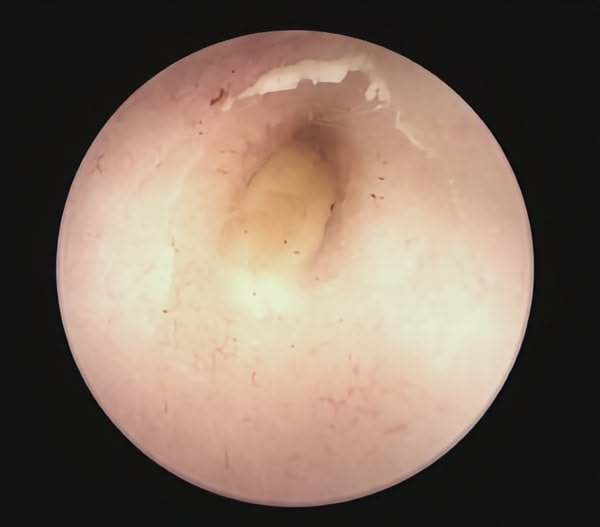

Trois cas résultent de l'extension d'une otite. Ces patients étaient présentés pour ataxie et l'un d'entre eux présentait également des crises convulsives partielles. Dans les trois cas, un examen scanner a mis en évidence une otite moyenne associée à une lésion intracrânienne extra-axiale adjacente, évoquant un empyème méningé. Dans le premier cas, un traitement antibiotique probabiliste permet la résolution des signes cliniques. Dans le deuxième cas, des prélèvements par vidéo-otoscopie permet d'identifier la présence de Staphylococcus felis. Un traitement antibiotique ciblé entraîne la résolution des signes cliniques. Dans le troisième cas, l'examen vidéo-otoscopique permet l'identification de Pseudomonas spp. Malgré une antibiothérapie adaptée, l'état clinique du patient se détériore. Un nouvel examen scanner montre une aggravation de l'empyème méningé. Une craniotomie est réalisée et permet le débridement de l'empyème. Cette intervention, associée à une corticothérapie et la poursuite de l'antibiothérapie, permettent la résolution des signes cliniques.